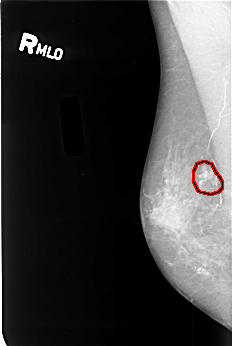

B_3380_1.RIGHT_MLO

FILE: B_3380_1.RIGHT_MLO.OVERLAY

TOTAL_ABNORMALITIES 1

ABNORMALITY 1

LESION_TYPE CALCIFICATION TYPE PUNCTATE-PLEOMORPHIC DISTRIBUTION CLUSTERED

LESION_TYPE MASS SHAPE IRREGULAR MARGINS ILL_DEFINED

ASSESSMENT 4

SUBTLETY 3

PATHOLOGY MALIGNANT

TOTAL_OUTLINES 1

BOUNDARY